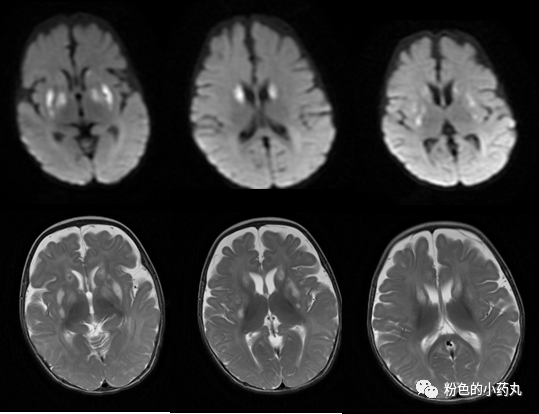

因遗传特征不同MRI通常呈异质性。一般来说,病灶分布对称。可分为三型: 基底节型、脑干型及白质型。

T2/FLAIR高信号,累及基底节中以壳核最多见,累及丘脑中以背侧丘脑内侧近第三脑室最多见。文献报道,双侧对称的壳核受累是必备的特征,尾状核、苍白球及丘脑可同时受累,但绝不会在壳核不受累的情况下单独出现。脑白质、皮层及小脑受累少见,病变范围较广可累及胼胝体和内囊。

T1常表现为低信号,但可见部分高信号,有一定强化。

DWI 的信号变化在时间分布上呈多样性,急性期DWI 病变可见弥散受限。

图 病例1

图 病例2

图 病例3

图 病例4